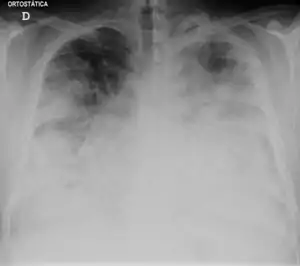

Those with Legionnaires' disease usually have fever, chills, and a cough, which may be dry or may produce sputum. Almost all experience fever, while around half have cough with sputum, and one-third cough up blood or bloody sputum. Some also have muscle aches, headache, tiredness, loss of appetite, loss of coordination, chest pain, or diarrhea and vomiting. A significant percentage of those with Legionnaires' disease have gastrointestinal symptoms, as well as neurological symptoms, including confusion and impaired cognition.[34][35]

The most useful diagnostic tests detect the bacteria in coughed-up mucus, find Legionella antigens in urine samples, or allow comparison of Legionella antibody levels in two blood samples taken 3–6 weeks apart. A urine antigen test is simple, quick, and very reliable, but only detects L. pneumophila serogroup 1, which accounts for 70% of disease caused by L. pneumophila, which means use of the urine antigen test alone may miss as many as 30% of cases.[36][37][38] This test was developed by Richard Kohler in 1982.[39]

Macrolides (azithromycin or clarithromycin) or fluoroquinolones (levofloxacin or moxifloxacin) are the standard treatment for Legionella pneumonia in humans, with levofloxacin being considered first line with increasing resistance to azithromycin. Two studies support superiority of levofloxacin over macrolides, although not FDA approved.[40]